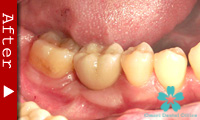

歯が全くない場合

下顎の歯が1本もない場合の修復には、インプラントが良く利用されます。

インプラントのヘッド部をバー状の維持装置で連結し、その上に取り外し式の入れ歯をしっかりと固定することができます。